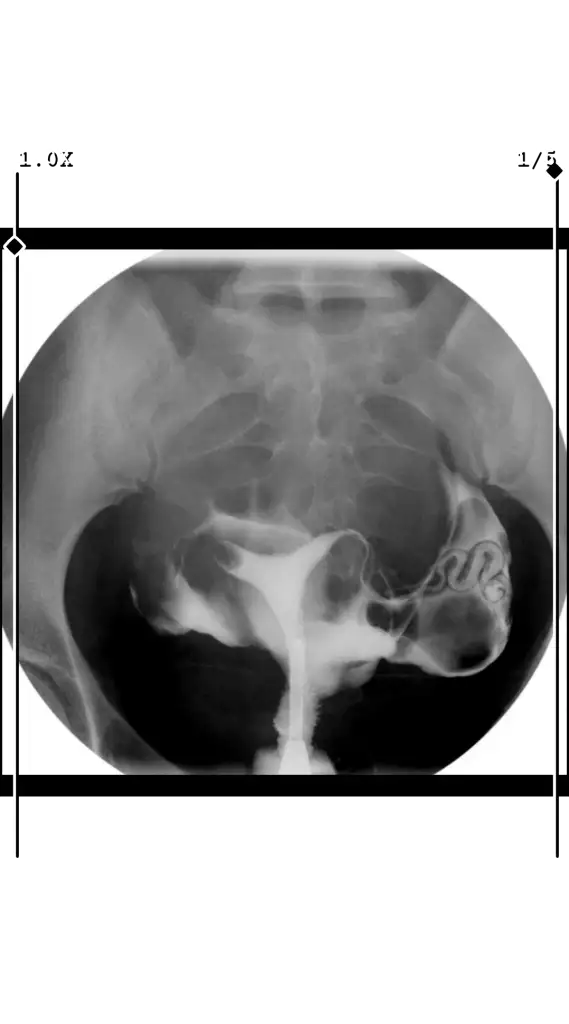

Acil rahim filmi yorumlarmisiniz